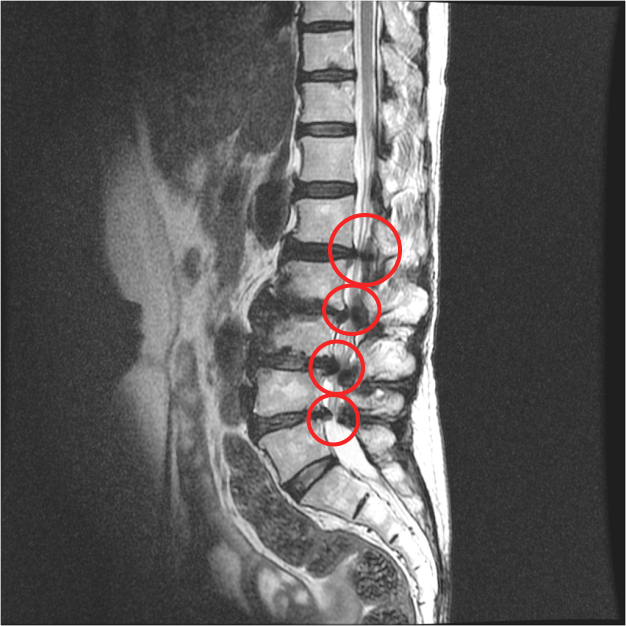

협착증 치료에 대한 잘못된 생각 두 번째, 치료만 하면 끝이라는 생각입니다. 많은 분들이 협착증 치료는 원인을 깨끗하게 해결할 거라고 기대합니다. 그래서 치료만 받으면 다 끝난다고 생각하니까 치료에 대해 조급증을 갖습니다. 그래서 조급하게 치료를 결정하고, 치료를 받고 나면 모든 게 끝날 거라 기대합니다. 이 경우 무엇이 문제가 되느냐? 모든 게 끝났다고 생각하니까 관리를 안 하고, 이게 많은 문제를 일으킬 수 있습니다. 한번 늙어버린 건 다시 젊어지지 않으므로, 치료 후에 어떤 치료를 받고 좋아졌든 지속적인 세심한 관리와 재활운동이 반드시 필요합니다. 치료만 받으면 끝이라고 생각하고 조급함을 가질 경우 생길 수 있는 문제를 먼저 수술 후 발생할 수 있는 문제부터 말씀 드리겠습니다. 협착증 수술은 문제를 일으키는 가장 큰 원인인 퇴행된 척추관 내의 황색인대를 제거하게 되는데, 퇴행이 가장 심한 부분을 수술로 제거하고 나사를 박아 고정시키게 됩니다.

그런데, 보시면 협착증은 이 부분만이 아니라 주변 부분도 다 퇴행되어 있습니다. 그래서 고정술을 한 이후에 이 부분이 구부리지도 펴지도 못하게 되기 때문에 이미 퇴행된 주변 마디에 부담을 주게 됩니다. 주변 마디가 더 많이 구부렸다 폈다가 해줘야 하는 것이죠. 그런데 앞서 말했듯이 협착증 환자는 이미 주변 위아래 마디도 퇴행되어 약해진 상태인데, 추가적으로 부담을 주니까 시간이 흐르면 주변 부위도 문제가 생기게 되는데요. 이것을 인접분절질환이라고 합니다. 일반적으로 척추유합술 후 이러한 문제가 많이 발생하기 때문에 인접분절질환이라는 이름까지 만들어져 있습니다. 이러한 인접분절질환은 특히 수술 후 관리를 잘 못하면 당연히 더 잘 생기기 때문에 유합술을 했다면, 이 인접분절질환이 생기지 않도록 관리를 세심하게 잘 해줘야 합니다.